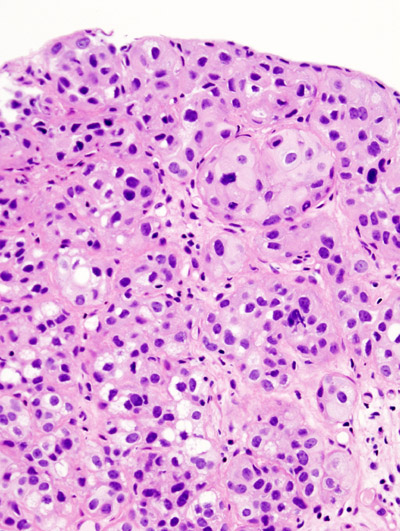

When examined under a microscope, the most common variant of renal cell carcinoma shows clear cytoplasm or a clear cell type.

Renal Cell Carcinoma (RCC)

Renal cell carcinoma (RCC) is a malignant cancer cells are located in the lining of kidney tubules, which are incredibly tiny tubes. This condition is known as renal cell carcinoma.